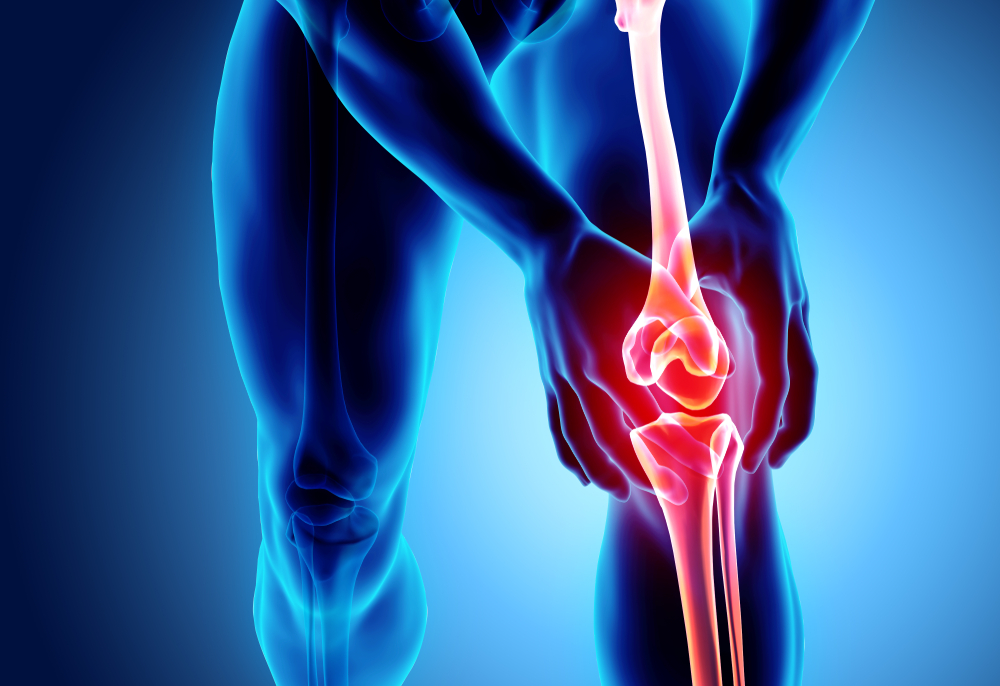

En otras palabras, ‘la rodilla del corredor es un síndrome que consiste en un dolor en la rótula y a su alrededor. Normalmente, se debe por la fricción constante en la articulación de la rodilla’, dice Jackeline Equité, coordinadora de fisioterapia de Blue Medical. Además del dolor en la parte externa de la rodilla, Gómez agrega que podría haber dolor, enrojecimiento y disminución en la función de esta.

En el diagnóstico, Equité explica que ‘se presiona la rótula y se moviliza para evaluar si está completa o porosa por medio radiografías’. Lo primero que se debe hacer, dice Gómez, es identificar las causas del síndrome. De igual forma, el deportista debe modificar su entrenamiento en compañía de un entrenador personal. Según la fisioterapista, no es adecuado dejar de entrenar de repente cuando la rodilla está lesionada, ya que se pierde consistencia física y, lo único que sucede es que el dolor se queda suspendido. ‘Luego, al hacer actividades diarias como caminar o subir gradas, el dolor se reactiva’, explica.

Así que lo más adecuado es tratar la lesión con terapia para que los tejidos, que están inflamados al haber microrroturas, mejoren su condición. El paciente diagnosticado con rodilla de corredor debe ser asistido por fisioterapistas porque esto le permitirá desinflamar, regenerar el tejido y tener una correcta cicatrización.